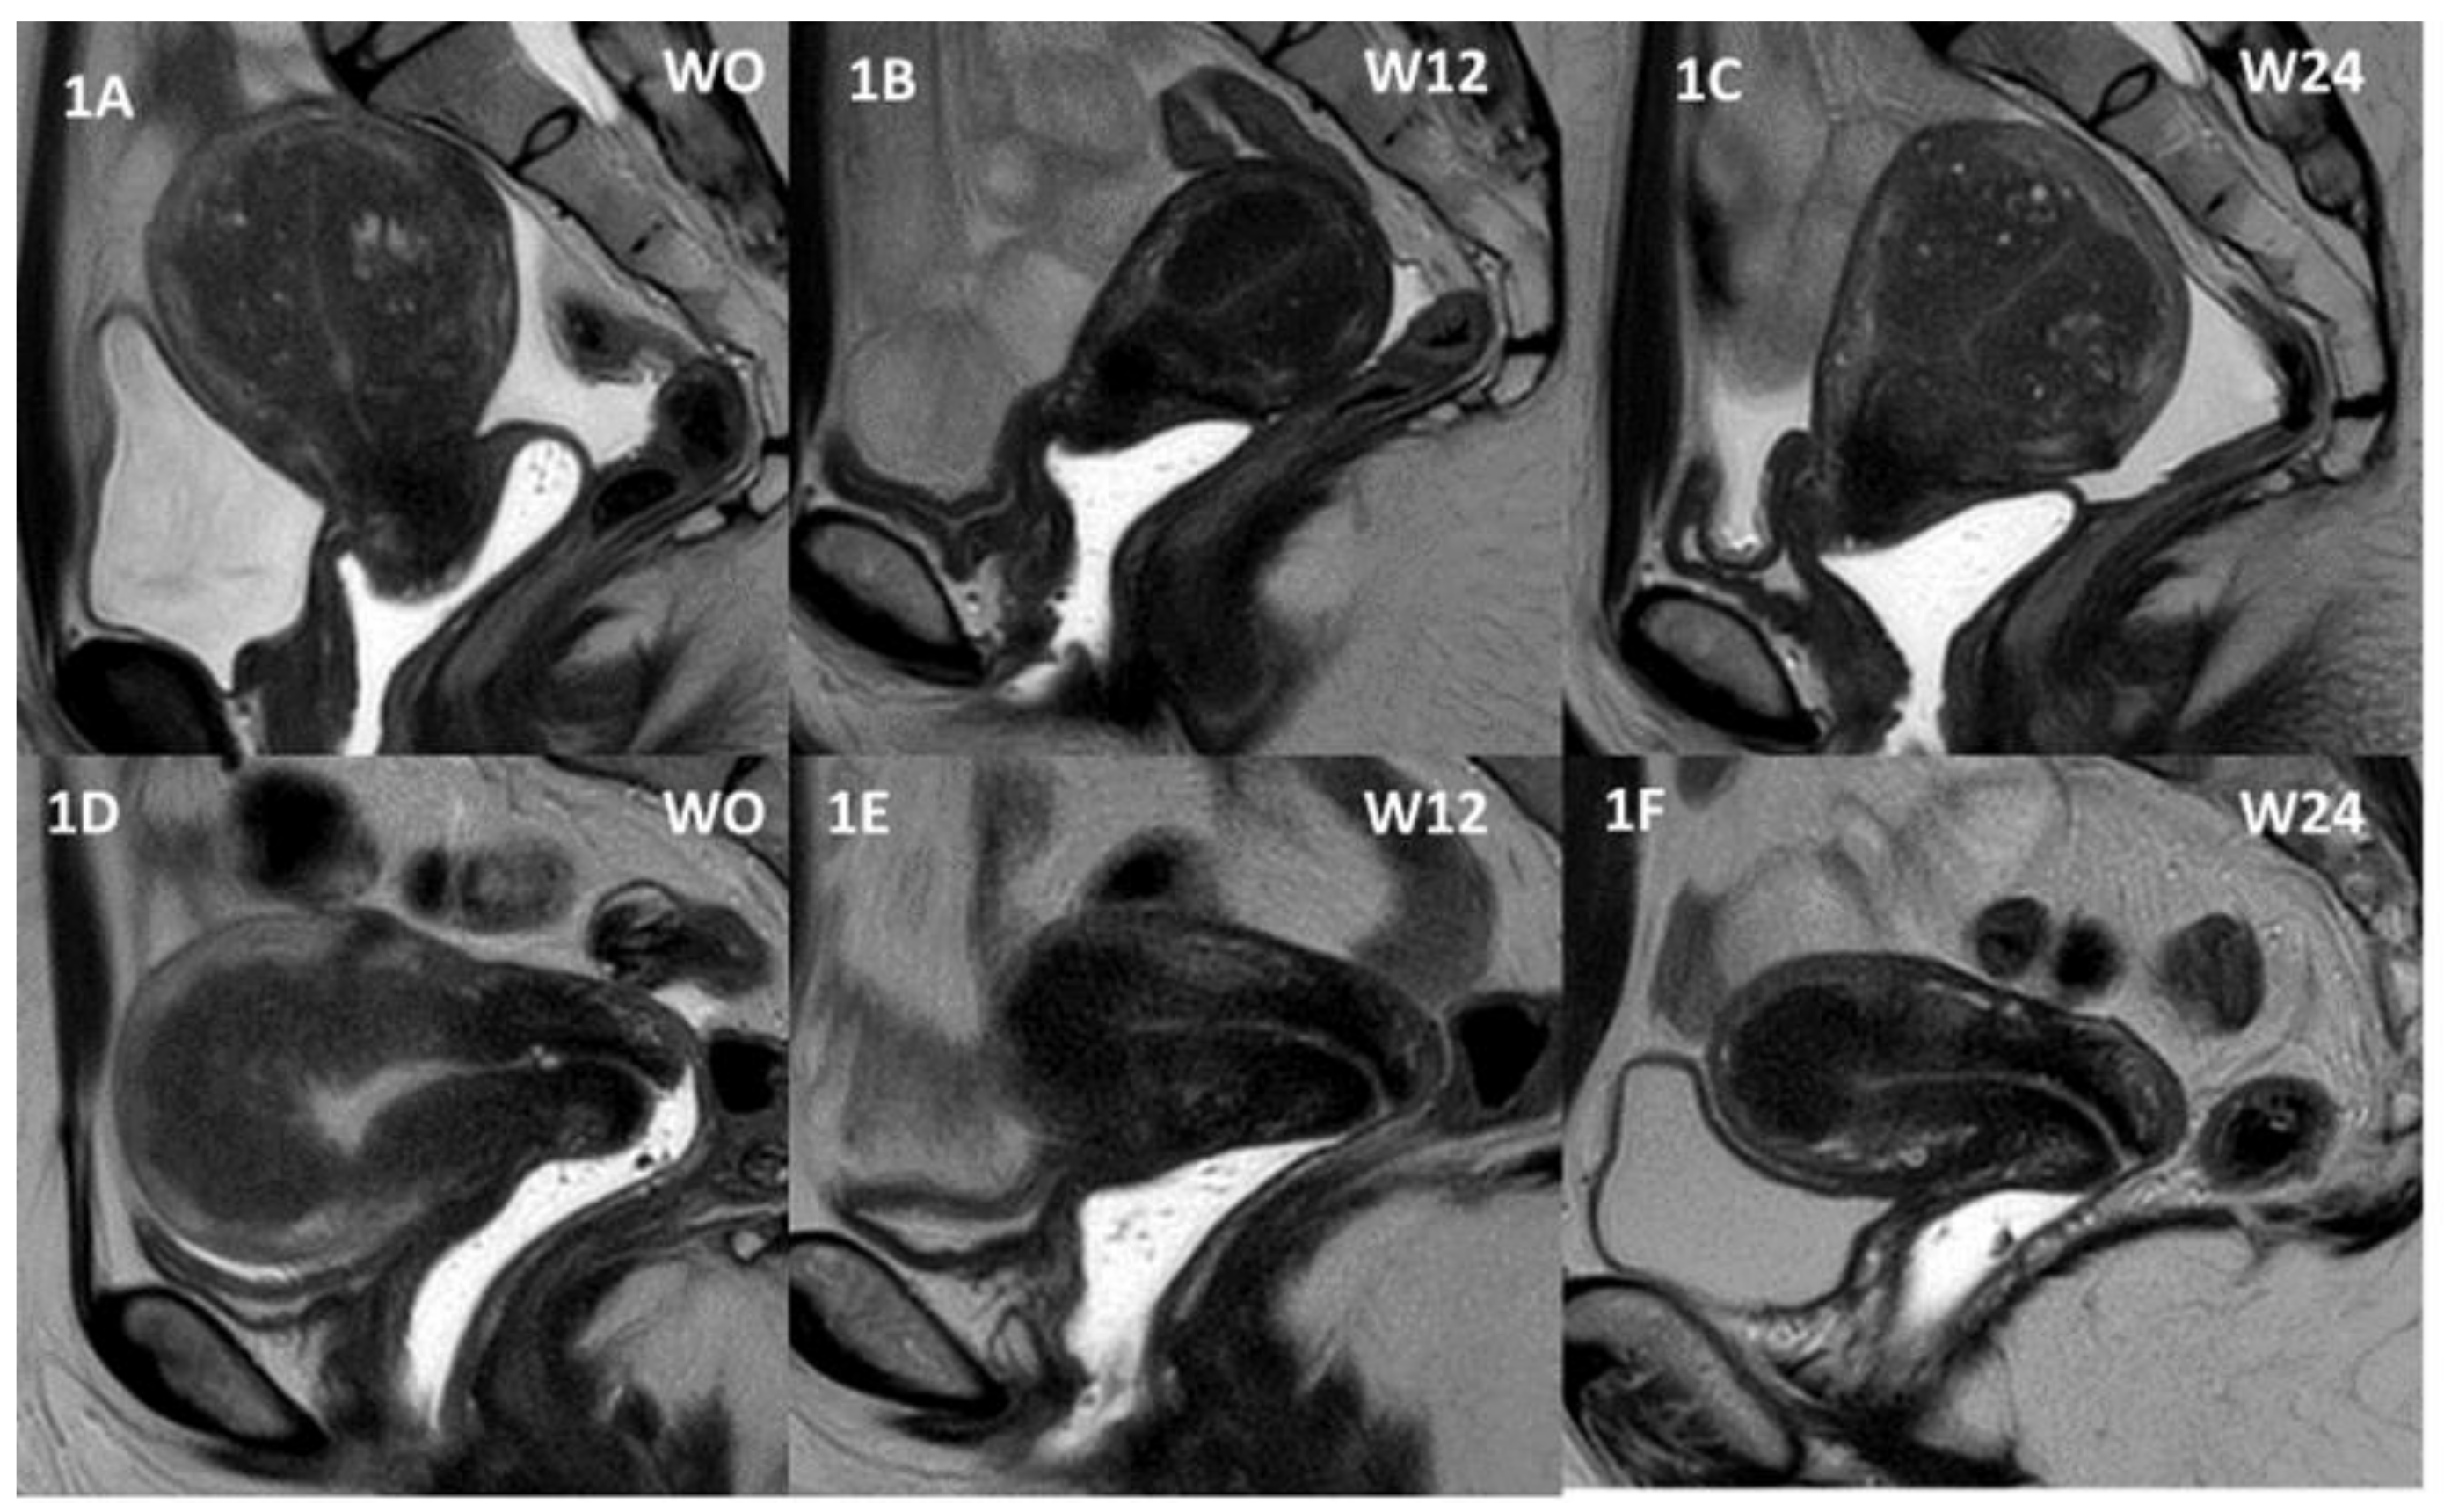

2. Materials and Methods

3. Results

3.2. Primary Efficacy Endpoint

3.3. Secondary Efficacy Endpoints